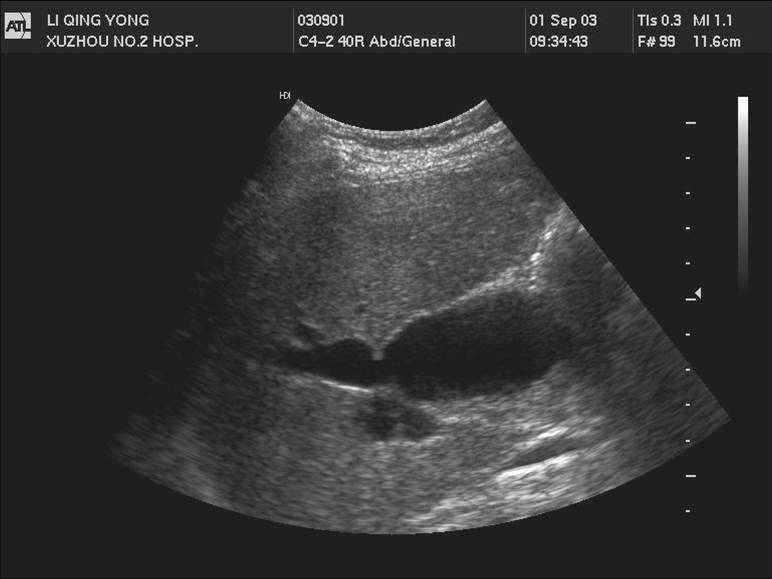

2 肝外胆管癌